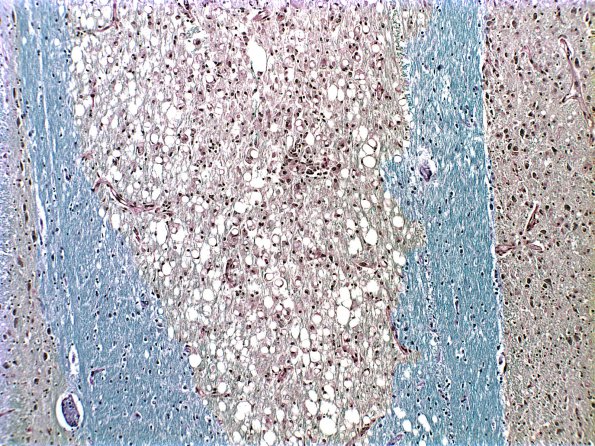

Washington University Experience | MYELIN (NON-IMMUNE MEDIATED) | Central Pontine Myelinolysis (CPM) | 9D1 CPM (Case 9) 1 LFB-PAS part A

9D1,2 Sequential sections stained for myelin (9D1, LFB-PAS) and axons (9D2, Bielschowsky) show nearly complete myelin loss with axonal sparing.